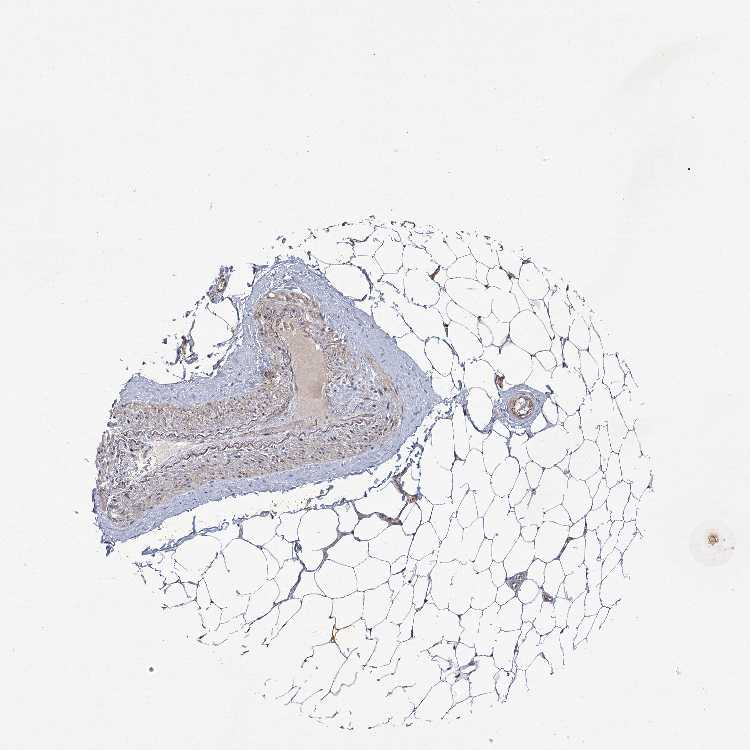

SOFT TISSUE 1 - Antibody stainingi

Antibody staining in the annotated cell types in the current human tissue is reported as not detected, low, medium, or high, based on conventional immunohistochemistry profiling in selected tissues. This score is based on the combination of the staining intensity and fraction of stained cells.

Each image is clickable and will lead to virtual microscopy that enables deeper exploration of all samples and also displays staining intensity scores, fraction scores and subcellular localization as well as patient and tissue information for each sample.

Antibody HPA037431

Chondrocytes Low

Fibroblasts Not detected

Peripheral nerve High

SOFT TISSUE 2 - Antibody stainingi